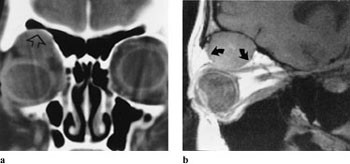

Lymfomer involverer oftest øvre del av orbita, inklusive øvre rette øyemuskel, og presser øyet nedover (fig 8 a, b). Det er svært vanskelig å differensiere røntgenologisk mellom lymfoid lesjon og lymfom i orbita, men der er også overlapping mellom de forskjellige typer histologisk. Karakteristisk er det, som også ved myositt, at muskelsenen er affisert. Både på MR og CT sees lymfomene som homogene, velavgrensede strukturer.

Kapillære hemiangiomer kan markere seg som blågrå misfarging av huden. CT viser isodens, lobulær masse med markert kontrastoppladning (fig 9 a, b). Venøse malformasjoner kan øke i størrelse ved forskjellig aktiviteter som f.eks. gråt eller andre manøvrer som forårsaker venøs trykkøkning. Angiografi er ikke godt egnet til å påvise slike malformasjoner. Valsalvas manøver utført under spiral-CT-undersøkelse kan demonstrere den klassiske økningen av lesjonens størrelse hvis pasienten samarbeider og er i stand å holde pusten i 20 – 25 sekunder. Slike lesjoner kan imidlertid best påvises ved dopplerfargestrømsultralydundersøkelse.